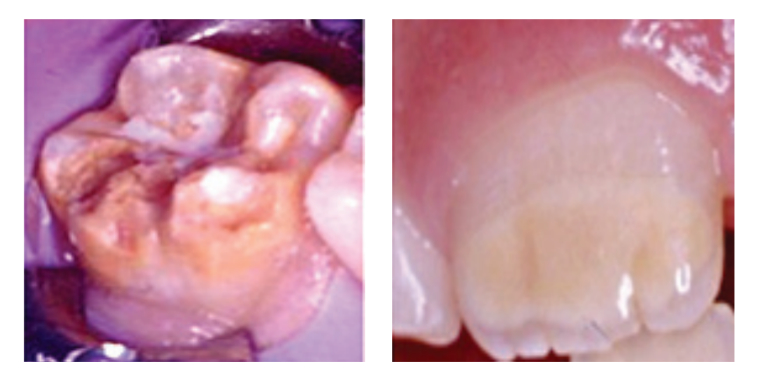

Molar Incisor Hypomineralization (MIH) is a developmental condition affecting the enamel of first permanent molars and frequently the permanent incisors. The condition is characterised by qualitative enamel defects that may present as demarcated opacities, enamel breakdown, hypersensitivity, and increased susceptibility to caries.

Children affected by MIH often experience discomfort, difficulty with oral hygiene, and aesthetic concerns. Early diagnosis and appropriate management are therefore essential to minimise complications and maintain oral health.

Restorative treatment options may include minimally invasive approaches, adhesive restorations, or full coverage restorations depending on the extent of enamel breakdown.